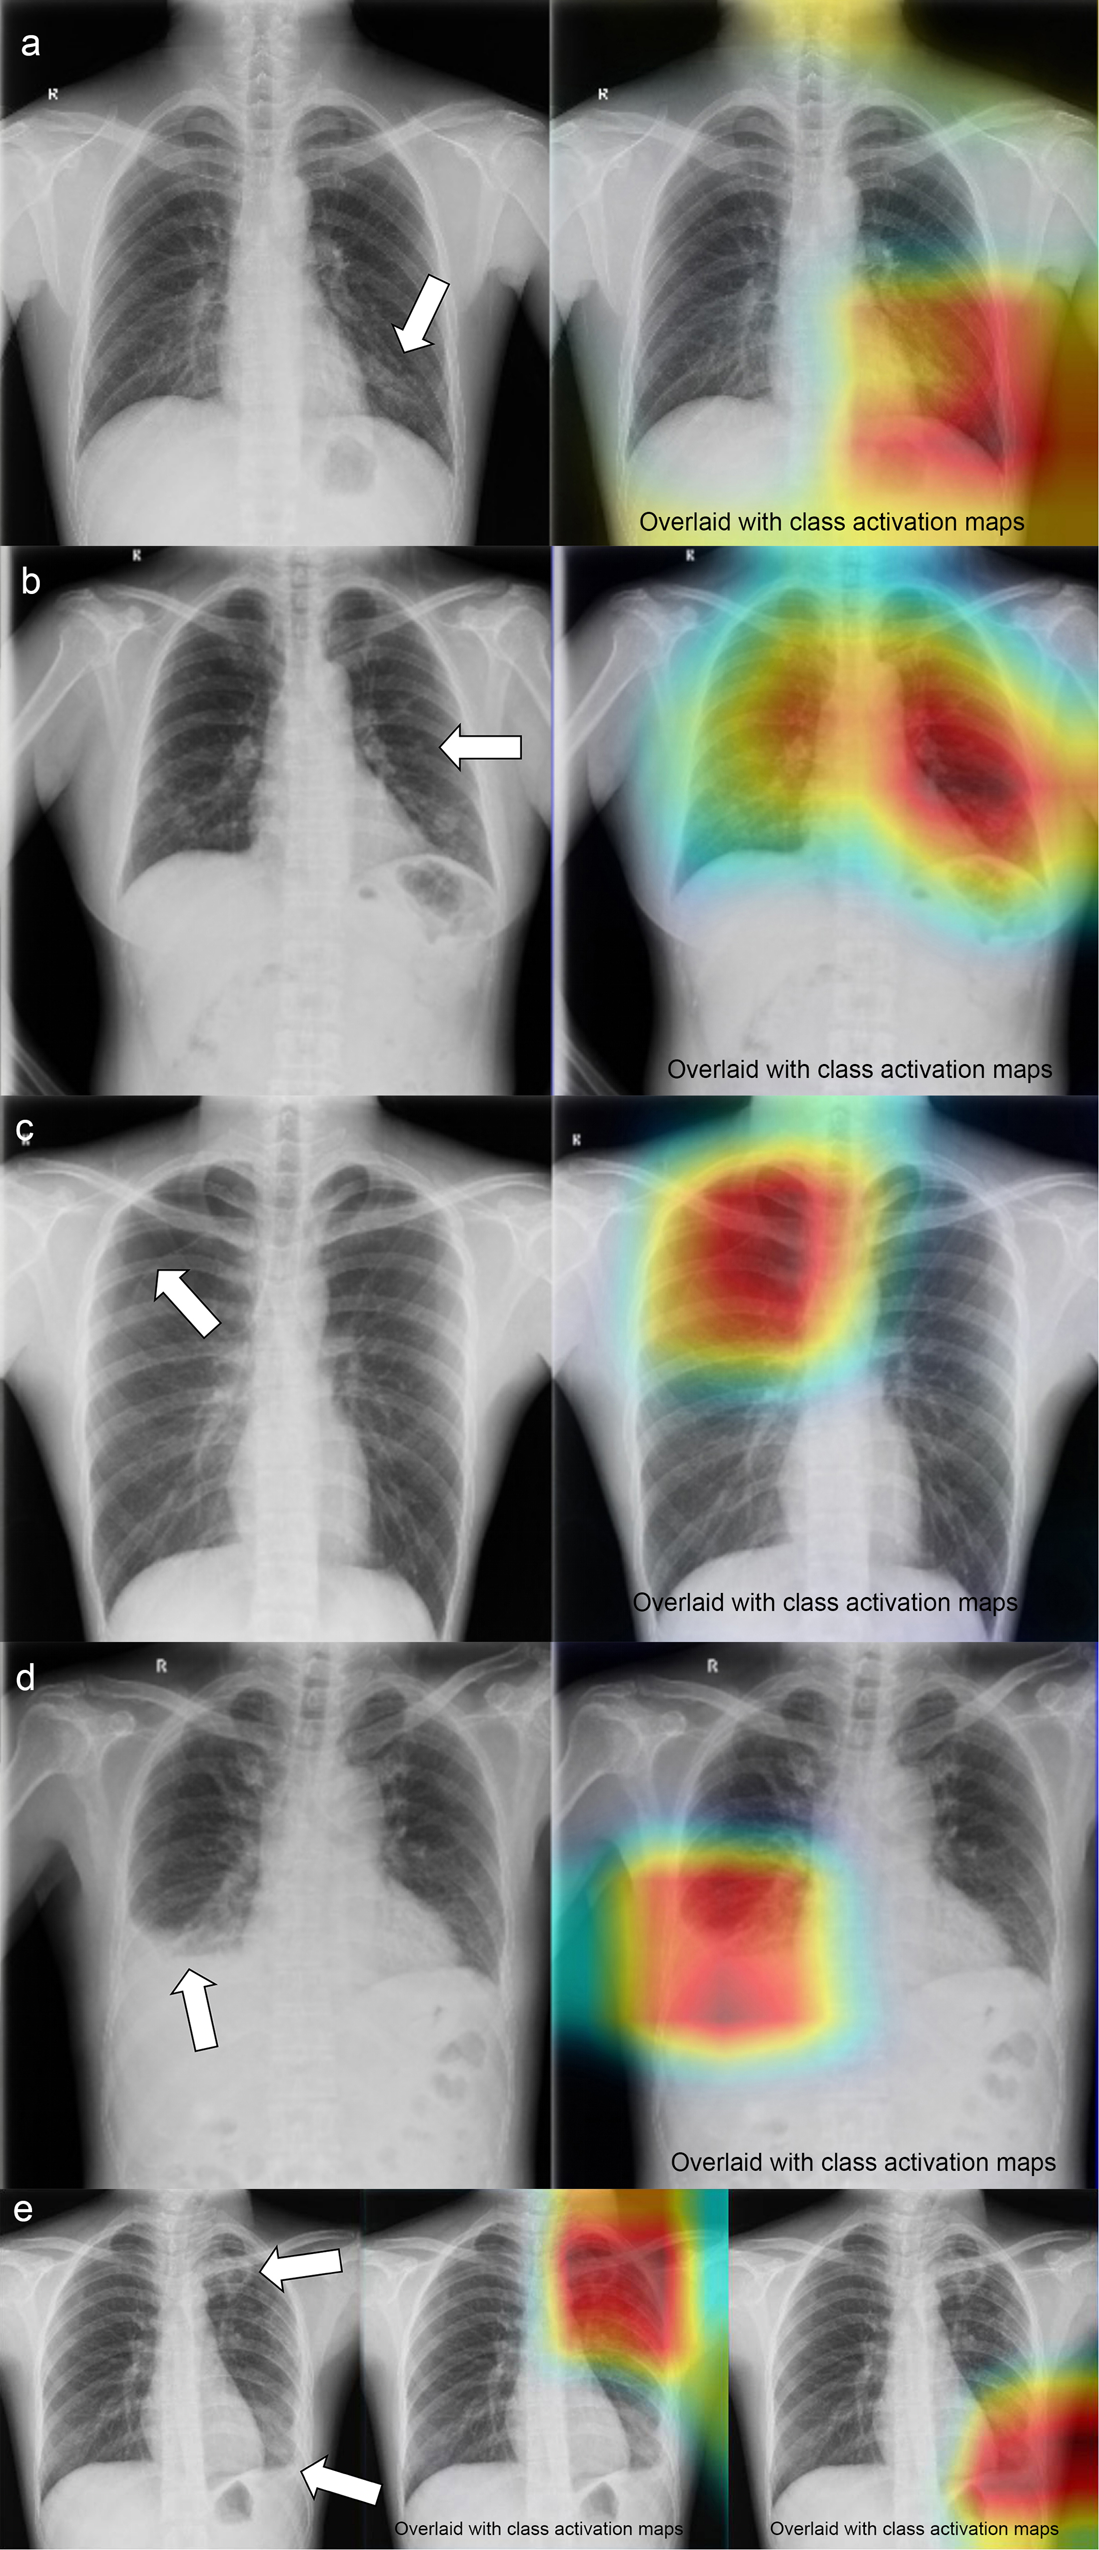

Fig. 5: Representative chest radiographs overlaid with class activation maps (CAM) showing the active area of convolutional neural network (CNN).

a The inferior lung field of the left lung is overlaid by CAM, which reveals a patchy density (white arrow). The CNN noted that this case had a “patchy consolidation” sign, while the other 24 abnormal signs were absent. b The middle and lower fields of the left lung are overlaid by CAM, which reveals a pulmonary nodule (white arrow). The CNN indicated that this case had a “nodule” sign, while the other 24 abnormal signs were absent. c The upper right lung is overlaid by CAM. The CNN indicated that this case has a “pneumothorax” label. The radiologists confirmed this finding and found visible visceral pleural margins (white arrow), but there was no lung texture outside this line. The other 24 abnormal signs were absent. d The lower right lung is overlaid by CAM. The CNN indicated that this case has a “hydrothorax” sign. The radiologists confirmed this finding and identified an air-fluid level (white arrow). e The upper field and lower field of the left lung are overlaid by CAMs. The CNN indicated that this case had “patchy consolidation” and “pleural effusion” signs. The other 23 abnormal signs were absent. The radiologists confirmed CNN’s findings (white arrows).